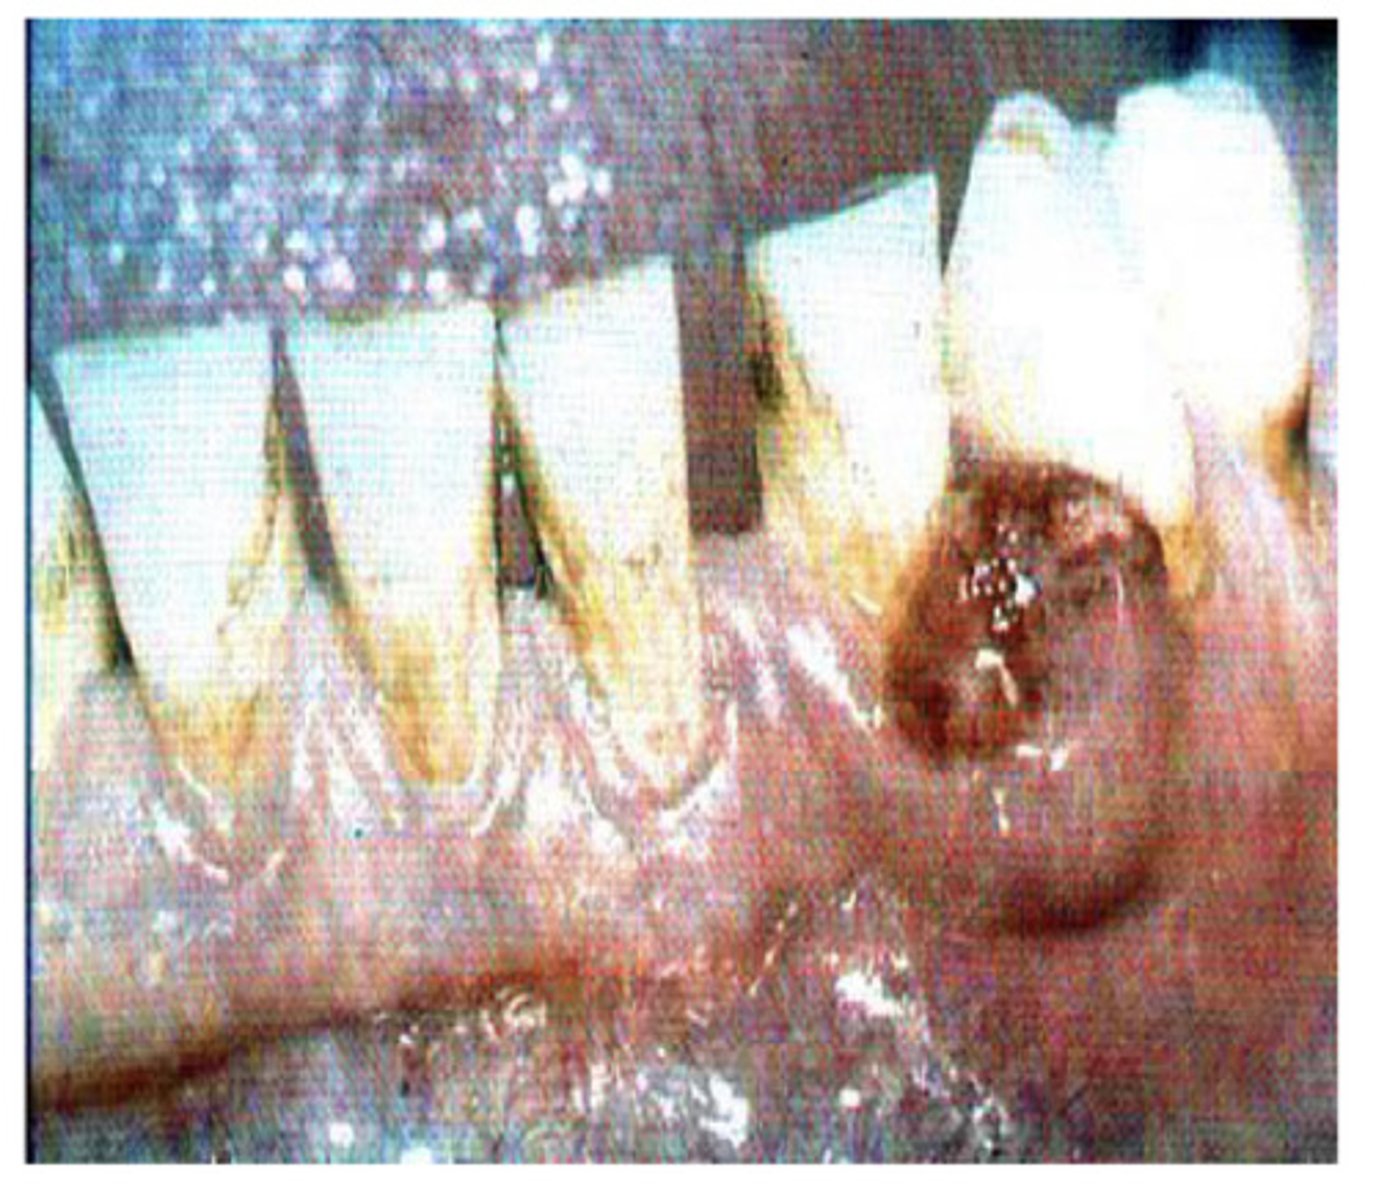

What is this?

Peripheral giant cell granuloma (epulis)

Unknown aetiology, red, haemorrhagic and soft, occasional superficial bone erosion - usually excised - what am i?